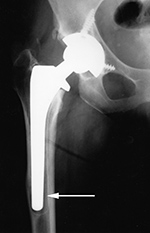

Non-infectious (aseptic) loosening of prosthetic components is

still the most common cause for hip implant failure and subsequent revision surgery. Loosening may be from mechanical stress with failure of the implant binding to the surrounding bone. There may be degradation of the cement-bone interface. Wear on the articular surfaces can produce tiny polyethylene particles or metallic particles which migrate from the joint and lessen bony healing giving subsequent osteolysis and eventual implant loosening (figure: focal osteolysis). The failure can occur at the prosthesis-bone interface, prosthesis-cement interface,

or cement-bone interface. Progressive development of radiolucent areas greater than 1 mm at these interfaces is worrisome for prosthesis loosening (figure: osteolysis at tip of femoral stem).

| Cemented total hip arthroplasty with focal osteolysis about the stem in zones, 2, 5, and 7. From Benjamin, 1994 |

There is radiolucency (arrow) around the entire femoral stem with a sclerotic margin and eccentric positioning of the stem. There is also thinning of the lateral femoral cortex. From Benjamin, 1994 |